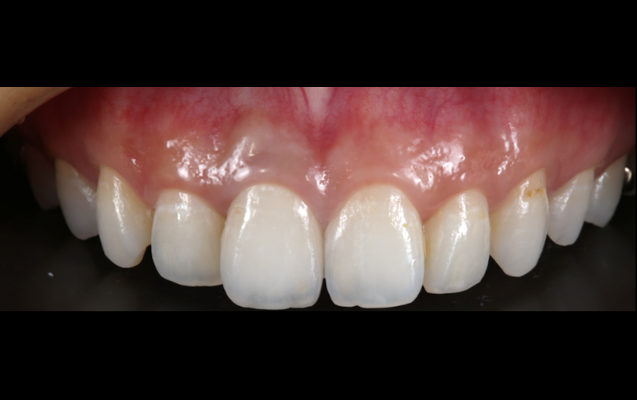

セラミッククラウンはご本人の歯を土台にしながら審美面を大きく改善でき、また噛み合わせや歯並びの矯正なども合わせて対応できることが特徴です。

当院では患者様一人ひとりに向き合った精密検査・診断を通してお口全体のバランスを整え、機能的で長持ちする審美治療としてセラミッククラウンをお作りしています。

(実際の症例)